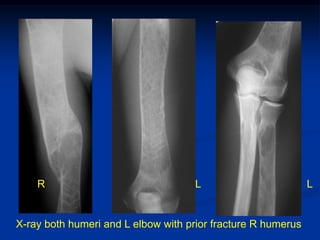

Case #1                Gaucher’s Disease

29 yr male with pathologic fracture femur and family history

of Gaucher’s disease

R                                L                        L

X-ray both humeri and L elbow with prior fracture R humerus